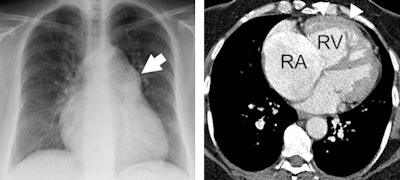

Left: Patient presenting with dyspnea. Contrast-enhanced CT chest demonstrates extensively calcified aortic valve with signs of heart failure. Right: Patient presenting with angina. The coronary CT angiography showed nonflow limiting coronary artery disease, but the full field-of-view reconstruction diagnosed lung cancer in the right middle lobe. Images courtesy of Dr. Edwin van Beek, PhD.Today the most relevant parameter for right ventricular function is measuring the ejection fraction by means of MRI. This parameter, which indicates how much percentage of its volume the heart can eject with each beat, is easy to measure and is an excellent parameter to predict outcome and to guide and monitor therapy, according to Dr. Jens Bremerich, head of the division of cardiothoracic imaging at the University Hospital of Basel in Switzerland. He will be presenting perspectives from cardiac imaging, specifically the role of the heart in cardiopulmonary disease.

Left: Patient with pulmonary hypertension. Conventional chest x-ray (A) shows enlarged pulmonary artery (white arrow); pulmonary circulation is compensated. Right: Contrast-enhanced CT yields enlarged right atrium (RA) and ventricle (RV). Hypertrophy of RV myocardium (arrowheads) indicate chronic RV pressure overload. Images courtesy of Dr. Jens Bremerich."This setup is a little more costly than usual, but it is very interesting and provides an excellent setting for cardiology and radiology residents to train," Bremerich said. "I think all hospitals should strive to carry out dual reading and reporting in selected cases, and in general there should be a low threshold for exchange with the referrer in cardiothoracic imaging."